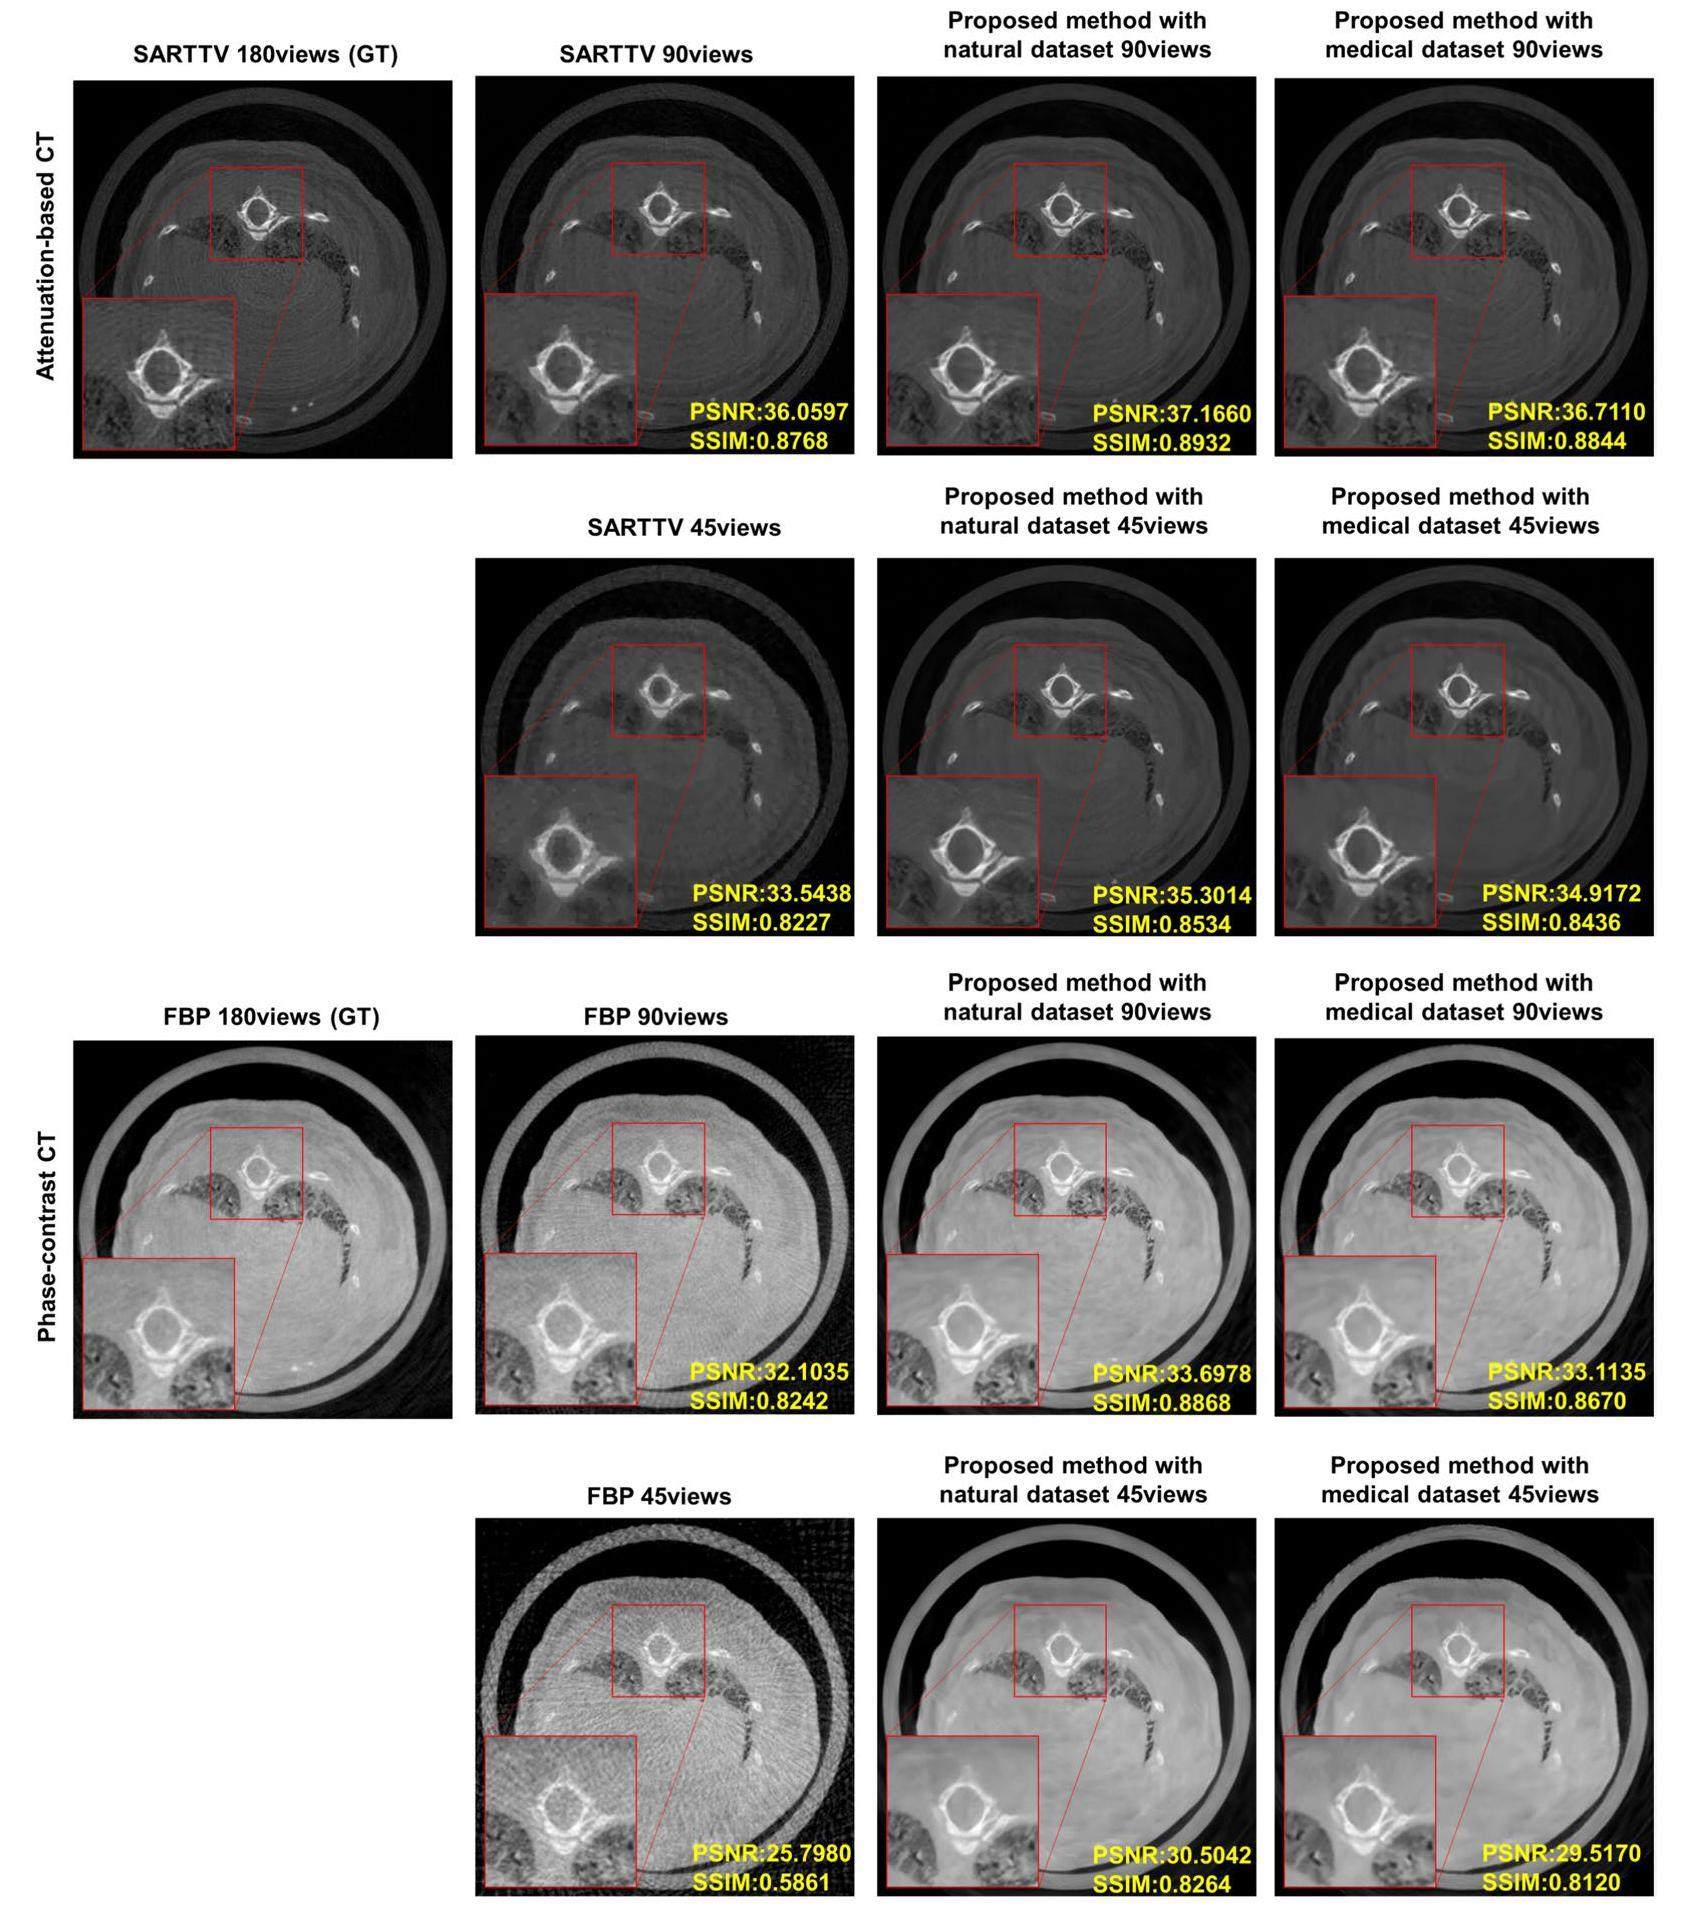

Experimental results under natural dataset and medical dataset

To verify the high generalization performance of the natural datasets, we compared the results generated by the networks trained on different datasets using attenuation-based CT and phase-contrast CT. This comparison is shown in Figure 4. For the attenuation-based CT, the GT image was defined as the reconstructed result obtained using the SART-TV algorithm from a 180-view projection. By contrast, in phase-contrast CT, the GT image is reconstructed using the FBP algorithm with 180-view projections. This selection was made because of the current prominence of the FBP algorithm in phase-contrast CT reconstruction, whereas the SART-TV algorithm is considered optimal for attenuation-based CT.

-202504-ok/1001-8042-36-04-016/alternativeImage/1001-8042-36-04-016-F004.jpg)

The attenuation-based CT and phase-contrast CT results are presented in Figure. 4 were obtained from the same mouse slice. Additionally, reconstructions were performed using 90 and 45 views to investigate the impact of data sparsity. The results shown in Figure 4 demonstrate that the network trained on the natural dataset outperformed that trained on the medical dataset for both attenuation-based CT and phase-contrast CT. The results obtained from the medical dataset exhibited a notably poorer performance, resulting in unclear and blurred local details. This discrepancy can be attributed to the limited image distribution of the medical dataset compared with the more diverse image distribution of the natural dataset. The greater diversity in the natural dataset contributes to its superior generalization performance when confronted with unknown samples. Furthermore, we conducted simulation verification using enough medical clinical CT data. The results are provided in Supplementary Information (SI). These results demonstrate that natural data can achieve outcomes comparable to those of a sufficient amount of medical data, even without prior medical knowledge.

In attenuation-based CT, soft tissue contrast is low, and sparse sampling leads to a significant decrease in image resolution, resulting in blurred structures. Conversely, in phase-contrast CT, the soft-tissue contrast is high, and the structures remain remarkably clear, even with only 45 views. These findings further validate the promising prospects of the proposed algorithm for phase-contrast CT.